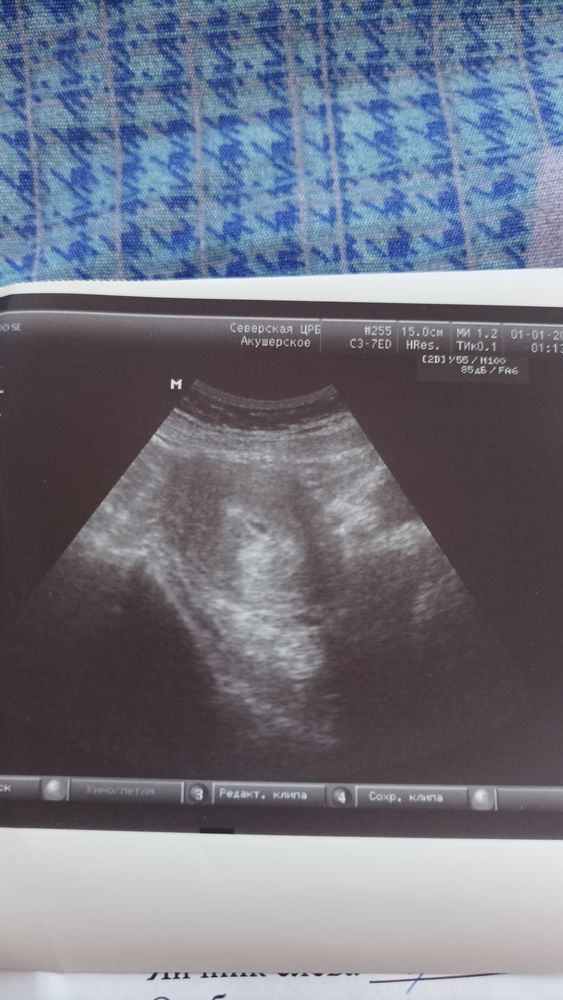

Деформировано оно может быть из-за тонуса, к следующему УЗИ все будет хорошо)

Добрый вечер. У меня так было с сыном. Приехала на сохранение, срок 4-5 недель был. По узи сказали, что деформация. После 3-4 дней повторное сделали и уже всё было гуд! Не накручивайте себя и верьте в лучшее. П.с. Мы просто очень рано делаем узи 😆 по себе знаю, такая же